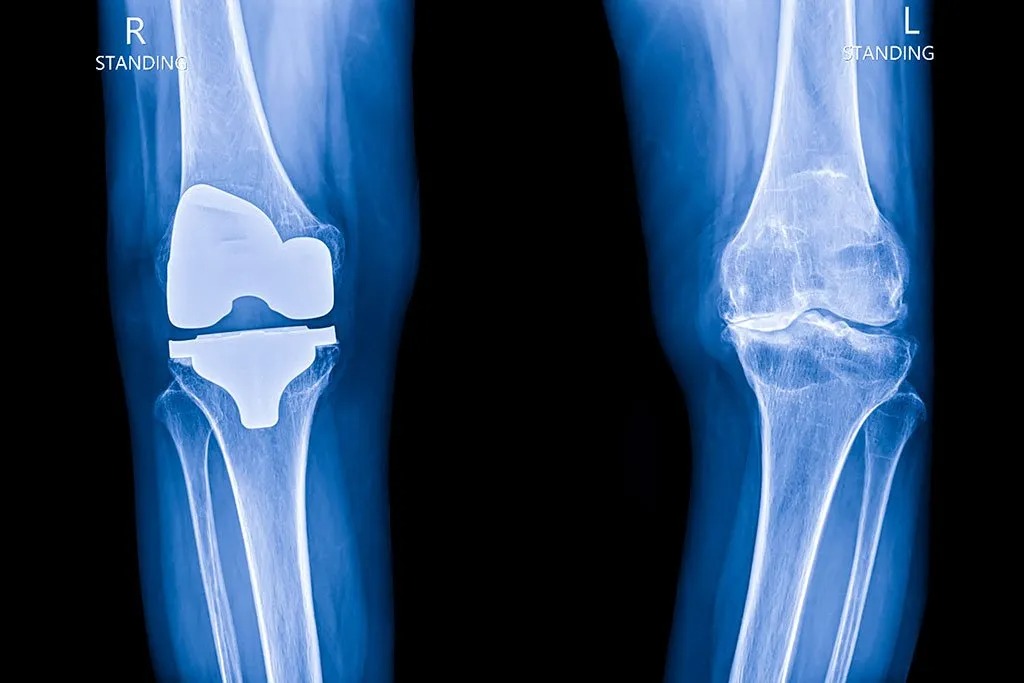

Knee Replacement in Lahore: What to Expect

Living with chronic knee pain can turn everyday tasks into painful challenges. For many people, especially older adults, this pain interferes with walking, climbing stairs, and even sleeping. If conservative options haven’t helped, a knee replacement in Lahore might be the solution you’re searching for. This guide explains everything you need to know about knee […]